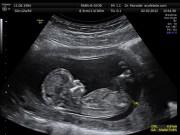

Chia sẻ trên một hội nhóm cách đây ít giờ, mẹ Hoàng Hường viết: “Khoe với các bạn em bé của mình lúc 22 tuần. Mình không biết là trong bụng em bé có thể ngáp đáng yêu thế này đâu. Giờ suốt ngày lôi ra ngắm ấy”.

Khoảnh khắc em bé ngáp và gãi đầu trong bụng mẹ.

Cùng với những dòng chia sẻ này, bà mẹ trẻ cũng chia sẻ một video ngắn ghi lại khoảnh khắc siêu âm thai khi em bé đang giơ tay gãi đầu và ngáp cực đáng yêu. Ngay khi video được đăng tải đã nhận về hơn 5 nghìn lượt yêu thích và rất nhiều bình luận khen ngợi và ai ai cũng mong muốn có con ngay.

Hình ảnh em bé ngáp được chụp từ video siêu âm thai.